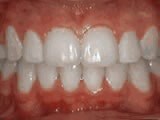

At age ten, patient had a big overjet with the top teeth protruding beyond the bottom. She had two phases of treatment. The first helped her jaws to grow more harmoniously and the second aligned her teeth and bite. At age 13, she was proudly displaying her new smile.